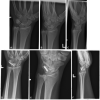

Background Chronic lunotriquetral (LT) ligament tears are a source of ulnar-sided wrist pain. Left untreated, complete tears of the LT ligament may progress to a volar intercalated segment instability deformity and eventual carpal arthritis. Various treatments have been proposed, one of which is LT arthrodesis. LT arthrodesis has been criticized for high rates of nonunion frequently requiring reoperation, and therefore has largely fallen out of favor. However, our experience has been quite different from the literature. This study examines a single surgeon's experience with LT arthrodesis over a 15-year period. Methods A retrospective review of the senior author's practice over a 15-year period was performed. All adult cases of LT arthrodesis for chronic LT injuries were included. Headless compression screw and cancellous bone graft from the distal radius were used for primary arthrodesis in all cases. The primary outcome was rate of union, and secondary outcomes were time to union, secondary or salvage procedures, and range of motion. Nonparametric statistical analysis was used to calculate differences in outcomes. Results Twenty-eight patients met inclusion criteria. The median age was 45.5 (interquartile range [IQR] 35-50) years and 75% were male. The dominant hand was most commonly affected. Eighty-six percent of patients achieved union, one patient required redo arthrodesis, and one patient went on to wrist salvage. Three patients developed a pain-free pseudoarthrosis. Median time to radiographic union was 8.8 (IQR 5.9-11.9) weeks. Conclusion Despite multiple previous reports, this study demonstrates that LT arthrodesis for chronic LT injuries is a safe technique with high rates of successful union. Further comparative studies are warranted to determine the optimal treatment for chronic LT injuries.